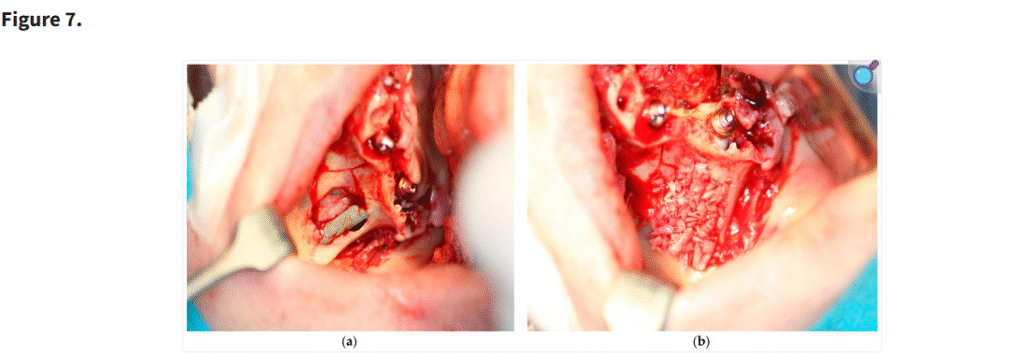

一部の症例では、長期的な統合を最適化し、軟組織の被覆を強化するために、ザイゴマインプラントの表面に骨片を添加した。このアプローチは標準的に必須とされるものではないが、臨床的判断および患者ごとのニーズに基づき選択的に適用された。本手技を示す高解像度写真をFigure 7に掲載した。

この写真は、ステラ法によるザイゴマインプラントの埋入(a)と、前方上顎洞から採取した骨片をザイゴマインプラント上に填入し、インプラントを骨膜から隔離するために用いた様子(b)を示している